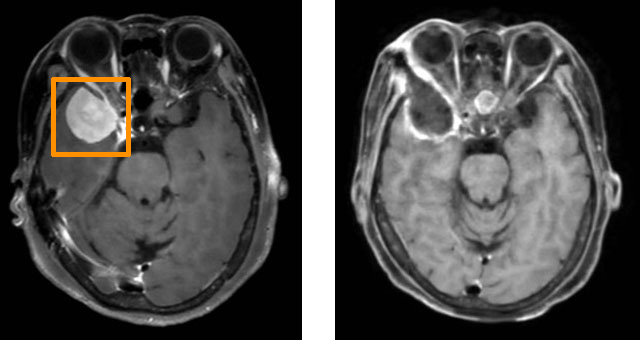

54岁的张女士(化名)因持续2个月的间歇性头痛就诊于我院神经外科。头颅CT检查显示其右侧颞叶巨大脑膜瘤,压迫邻近脑组织,直径达3公分,如不及时处理,患者可能会面临出现眼球运动障碍甚至失明的风险,手术治疗迫在眉睫。

左图为术前MRI,术后MRI(右图)显示肿瘤已全切除

该入路直达肿瘤附着的基底面,可以更好的控制肿瘤血供、减少出血,且不用牵拉脑组织,达到手术全切(Simpson分级0级),术后CT及MRI复查确认无残留。患者术后第2天即下床活动,较传统术式住院周期显著缩短。